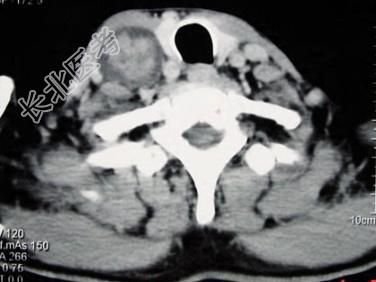

- 多项选择题男性,70岁, 右侧颈部无痛性肿块3个月,CT扫描如图所示, 请选择正确的描述和答案 ( )

A、右颈动脉间隙内见类圆形软组织肿块影,密度欠均匀,边缘光整

B、右侧颈静脉被推压至肿块外后方

C、右侧颈动脉被推压至肿块内后方

D、考虑迷走神经源性肿瘤

E、考虑交感神经源性肿瘤